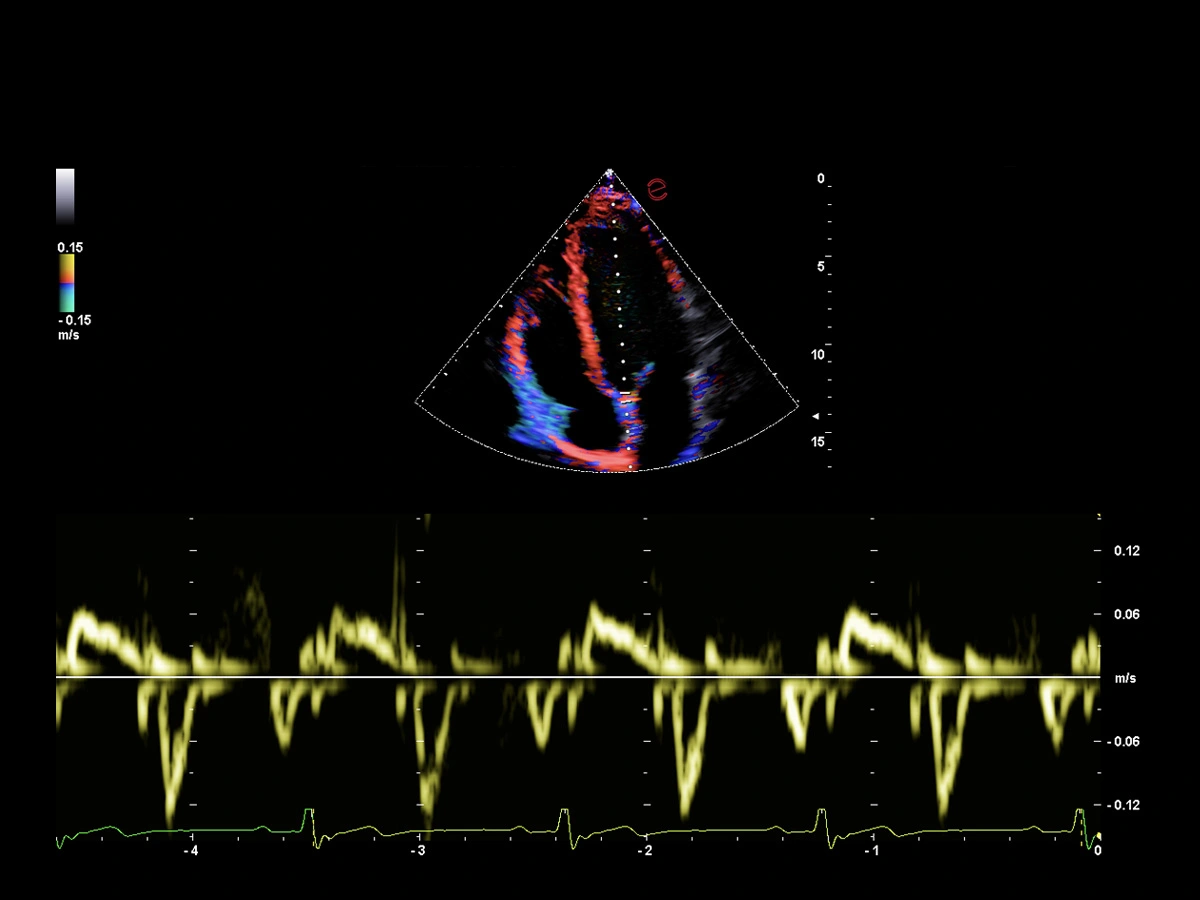

Innovative hemodynamic assessment with HyperDoppler

Esaote’s HyperDoppler technology provides an advanced visualization of intracardiac blood flow dynamics, offering clinicians an intuitive understanding of complex hemodynamics that goes beyond conventional Doppler imaging. By generating real-time vector maps, streamlines, and vortex formations, HyperDoppler enables the detailed assessment of diastolic function, ventricular dyssynchrony, and valvular abnormalities.

This unique flow visualization supports earlier detection of subtle dysfunction and increases diagnostic confidence, particularly in challenging cases such as heart failure, prosthetic valve evaluation, and structural heart disease. HyperDoppler’s zero-click, visually rich interface enables faster, more comprehensive exams, allowing cardiologists to make more informed clinical decisions.